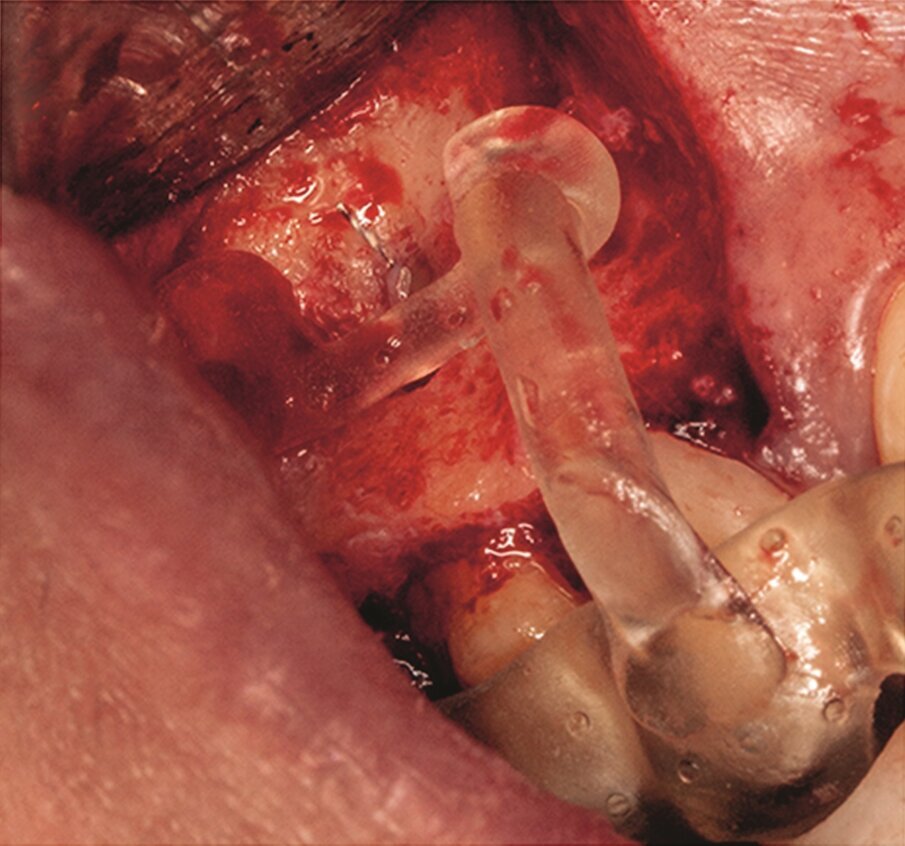

… with a saw mounted in a Piezotome CUBE LED handpiece, then the bone was cut and removed (g & h) …

… to access the apical area and perform the apicectomy, apical cavity preparation and retro-filling of the mesial and distal roots (i).

Under local anaesthesia, a full thickness mucoperiosteal flap was reflected and the printed template was used to mark the cortical window, which was cut with a Piezotome CUBE LED handpiece (ACTEON), removed (Figs. 1e–h) and then placed in sterile saline. An apicectomy was done (Fig. 1i), and the mesial canals were retro-prepared with ultrasonic tips (NSK) and filled with EndoSequence BC RRM Fast Set Putty (Brasseler). The cortical window was then placed back and stabilized with collagen sponges in the gaps (collagen tape, Zimmer Biomet; Figs. 1j & k), and the ‑ap was sutured using 6/0 prolene suture material (Corpaul).

Under local anaesthesia, a full-thickness mucoperiosteal‑ap was reflected, providing visualisation of the buccal bone (Fig. 2g), and the printed template was used to mark the cortical window (Fig. 2h), which was cut with a Piezotome CUBE LED handpiece, and the separated instrument was exposed (Fig. 2i) and removed (Fig. 2j). After apicectomy, retro-preparation was done using ultra sonic tips (ACTEON) and sealed with TotalFill BC RRM Fast Set Putty (FKG) (Fig. 2k). The ‑ap was sutured using 5/0 prolene suture material (Fig. 2l). The sutures were removed 72 hours postoperatively. After two years the patient came to our office for a follow-up radiograph, the tooth was asymptomatic and in function (Fig. 2m).

Fig. 2i: Separated instrument out of the root near the apical area of tooth #15.

Fig. 2j: Removed separated instrument.